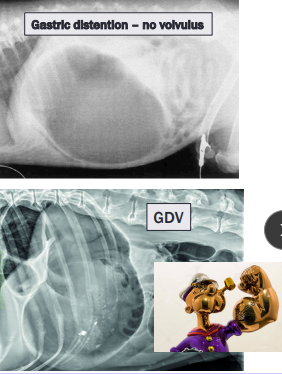

Gastric Dilatation-Volvulus (GDV)

Et: Rapid distention of stomach with air + volvulus @ axis

Compression of caudal vena cava → ↓ venous return → hypovolemic shock

EMERGENCY

Sig: Old, Lg, deep chest, rapid eating, aerophagia, raised food bowls, anxiety

Cs: non-productive retching, salivation, distention, tympany, tachycardia, weak pulse, shock

Dt: R-Lateral abdominal rads, double bubble, ↑ PCV, metabolic acidosis, coagulation defects

Tx:

Initial: LRS shock fluids, O2, Gastric decompression (NG tube or trocarization), Antibiotics

Sx: Emerg Gastropexy

Prevent: Prophylactic gastropexy, slow feeding, sm meals

Food Bloat

Et: over - eating

Cs: acute distention, panting, drooling, retching

Dt: r/o GDV →R-Lateral abdominal rads w/ uniform food-filled stomach

No volvulus present, rule out GDV

Tx: fluids, analgesics, gastric lavage

Supportive

resolves < 24-48hr, good Px